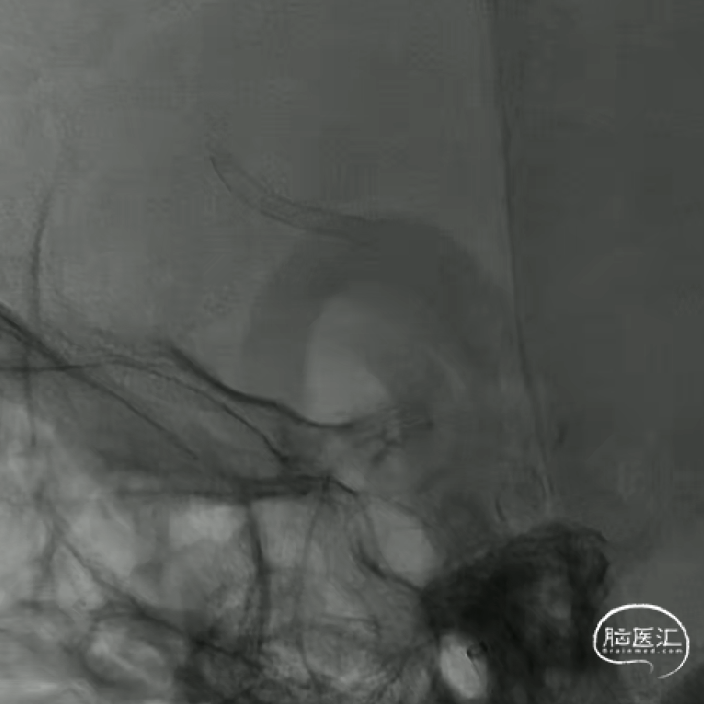

心玮DMC21微导管到位

颅内支撑导管上至C4段,心玮DMC 0.021inch 支架微导管通过颅内支撑导管,经微导丝超选至A4段。

如意输送到位

心玮“如意”FDD-250-20mm 血流导向密网支架输送到位。

如意远端释放

动脉瘤近端锐角弯曲,颅内支撑导管位置较低,且血管迂曲,无法提供很好的支撑和力的传导,故支架推送中阻力较大,需双手操作,给予支架推送杆一定张力。